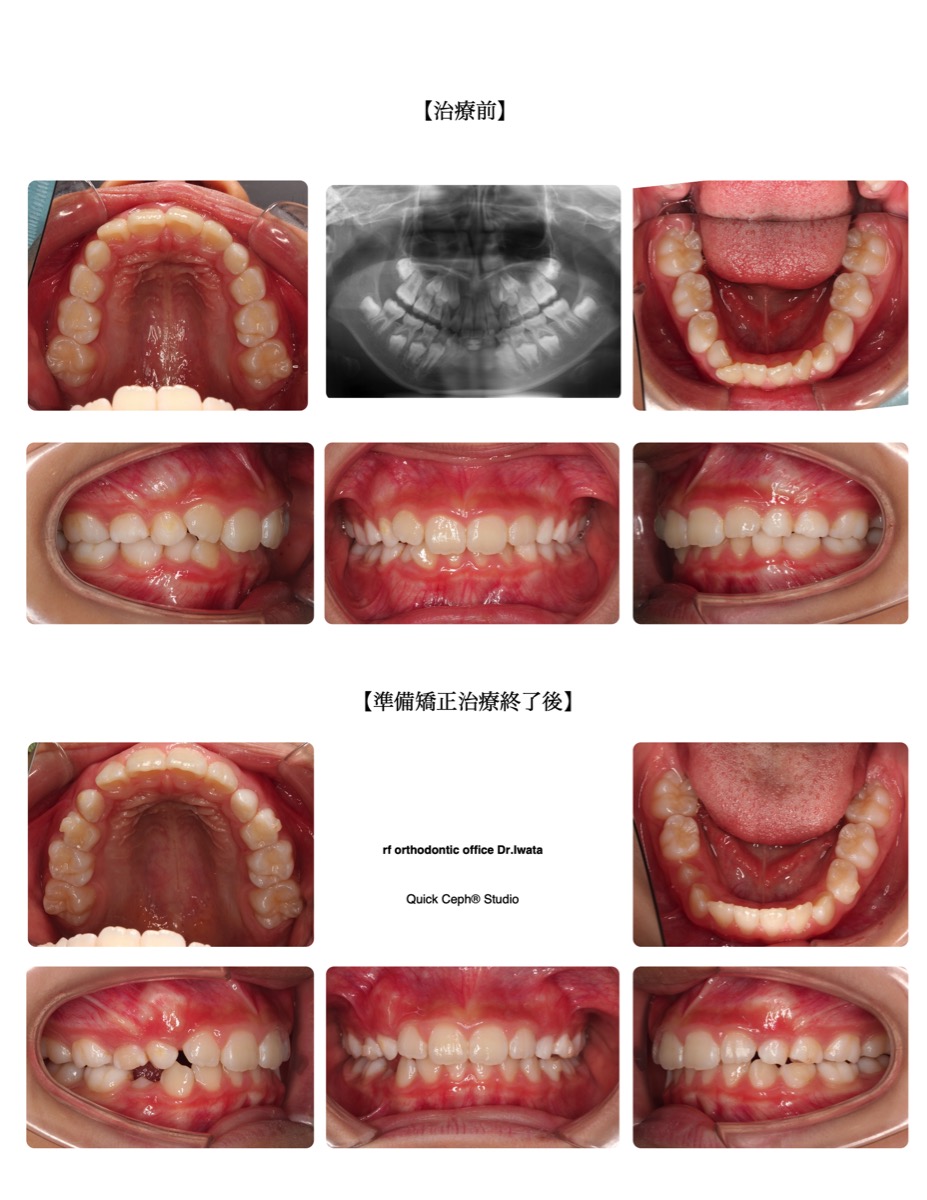

【主訴】下の前歯がガタガタで見えないので綺麗にしたい。

【主な症状】過蓋咬合 叢生